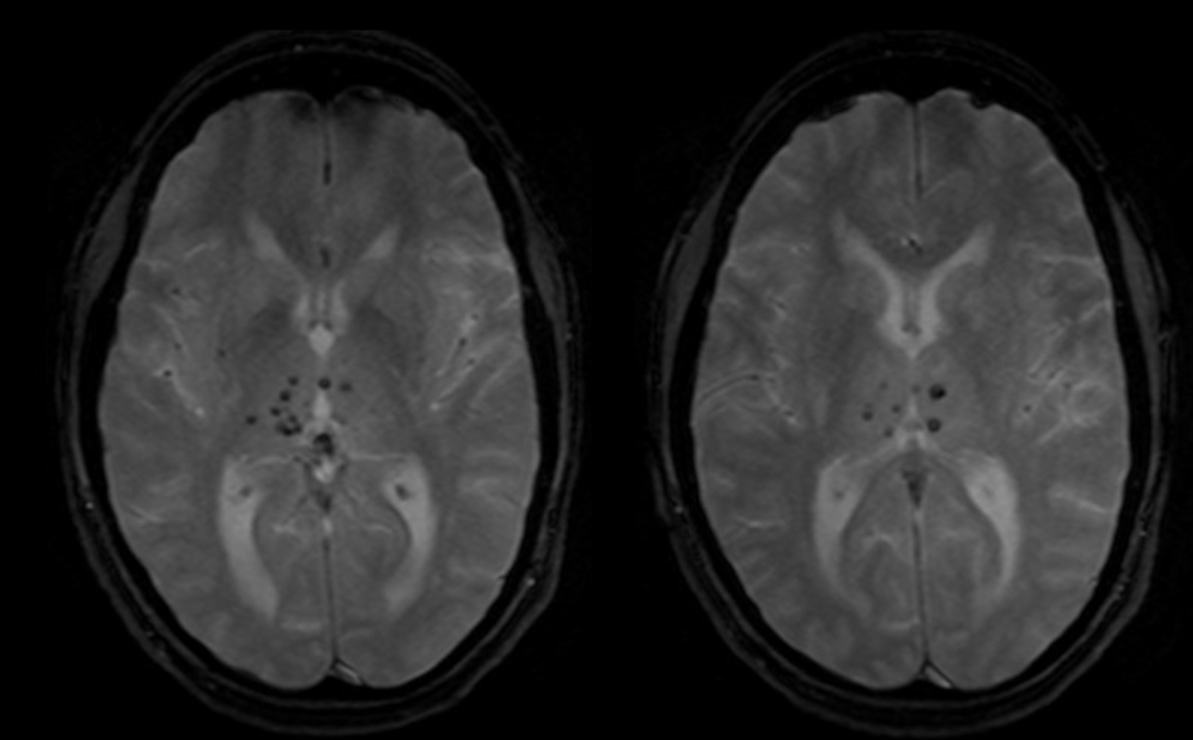

Σημείωση: Το τεχνικό σφάλμα μαγνητικής επιδεκτικότητας χρησιμοποιείται εποικοδομητικά για την ανίχνευση αιμορραγίας με χρήση ακολουθιών Τ2* GRE (2D Spoiled ακολουθία ή 3D SWI/SWAN), κυρίως στην περιοχή του εγκεφάλου (εικόνα) και γενικότερα του ΚΝΣ. Επίσης, χρησιμοποιείται στην τεχνική DSC Perfusion για τον δυναμικό έλεγχο της αιματικής διήθησης και στην λειτουργική Μαγνητική Τομογραφία (fMRI).

Εγκάρσια ακολουθία Τ2* GRE. Εποικοδομητική χρήση του τεχνικού σφάλματος μαγνητικής επιδεκτικότητας για την ανάδειξη μικροαιμορραγίας στον εγκέφαλο.